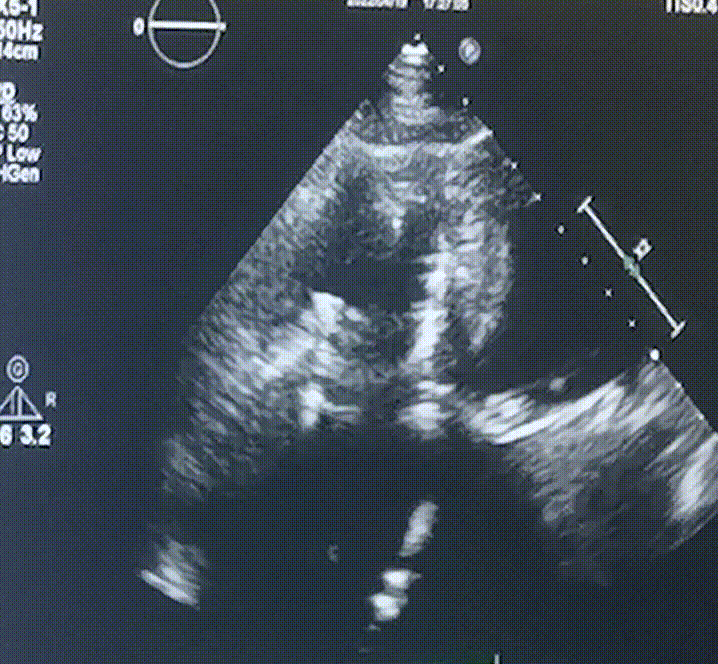

此次手術在全麻下進行,采用經右側頸靜脈入路。術中在經食道超聲和DSA的指引下多個維度精細調整輸送器角度,在達到正確位置后,逐步釋放瓣膜錨定裝置和盤片,最終完成瓣膜植入。術后患者右房壓明顯下降,術后超聲提示人工三尖瓣同軸性良好,瓣架固定牢靠,無反流和瓣周漏,血壓術后即刻上升20mmHg左右,手術后監(jiān)護室順利拔除氣管插管,3天后恢復良好,予以出院。

圖2.術后超聲